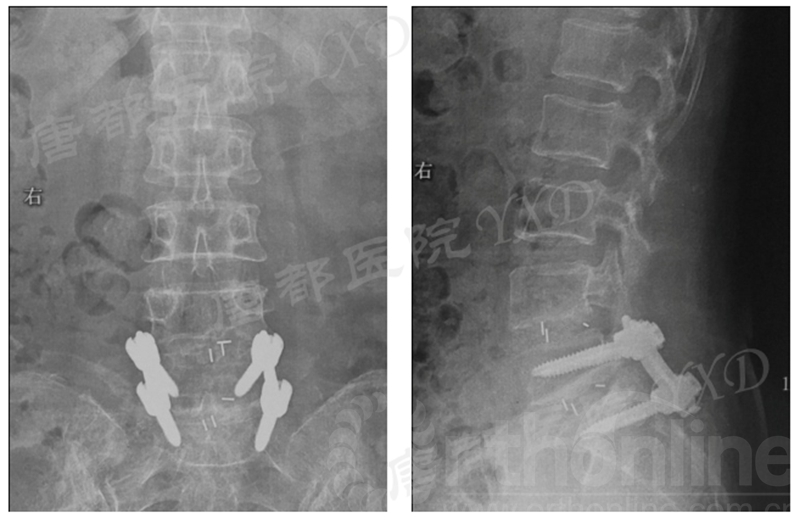

影像学检查:

诊断:腰椎椎间融合术后融合器后移

手术方案:显微镜辅助MI-TLIF腰椎翻修术

术后疗效:VAS左下肢1分、腰1分;左侧直腿抬高试验、加强试验阴性。